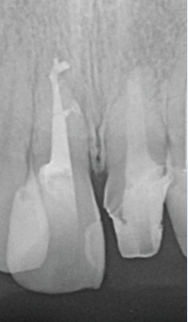

術前のレントゲン像とCBCT像(図11・12)元々根尖部が吸収し大きな根尖病変を有する症例。

CBCTでは唇側皮質骨が広範囲に渡って吸収している。歯根が短く歯冠:歯根比が悪い状態。

外科的歯内療法のアプローチも考えられるが、歯冠:歯根比を考慮し非外科的歯内療法のアプローチを選択。根尖部のゲージングは#100を示した。作業長1ミリアンダーに抵抗形態を付与し、根管充填材が根尖外に漏出することを避ける。MTAセメント(PRO ROOT ®️)にて根管充填を行う(図13)。

(図11)右上1番は歯髄描壊疸

左上1番大きな骨欠損を伴う慢性根尖性歯周組織炎を呈する

(図12)左上1番の根尖部付近の骨はCBCT上で

唇側皮質根も含め大きく欠損していることが確認できる

(図13)右上1番は根尖開口部をMTAシーラーと

ウォームガッタパーチャにて封鎖に務める左上1番は抵抗形態を付与し

MTA製剤が極力根尖外に漏出しないように注意しながら充填を行なった